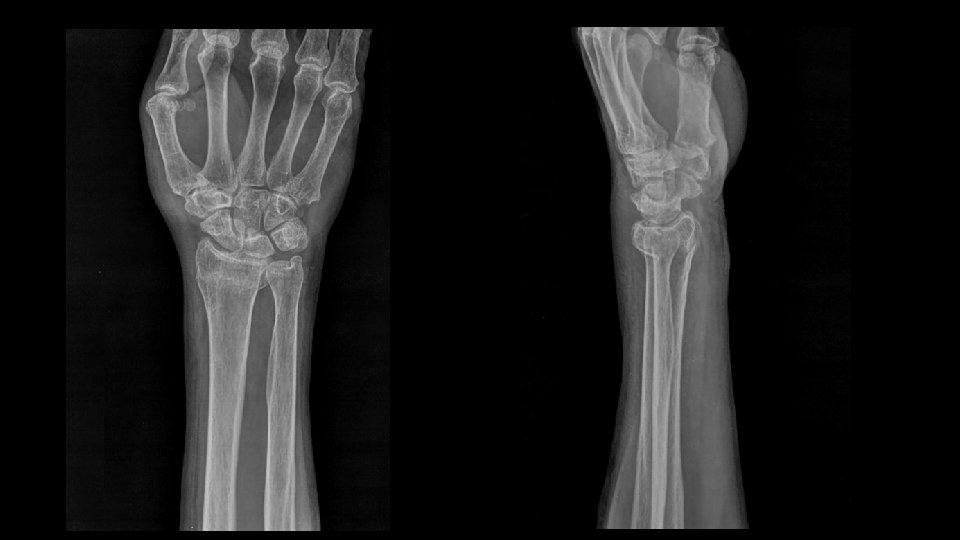

FX RADIOCUBITAL DISTAL FRACTURA DE COLLES O DE POUTEAU • Lesión traumatica mas frecuente de antebrazo distal. • > mujer, > 50 años. • Mano en dorsiflexion y antebrazo en pronación.

FX RADIOCUBITAL DISTAL FRACTURA DE COLLES • Fractura transversa de la metafisis distal del radio a 2 o 3 cm de la superficie articular. • Deformidad en dorso de tenedor. • 50 -60% asociado a fx del proceso estiloideo cubital.

FX RADIOCUBITAL DISTAL Variantes de la alineación de la Fractura de Colles

FX RADIOCUBITAL DISTAL